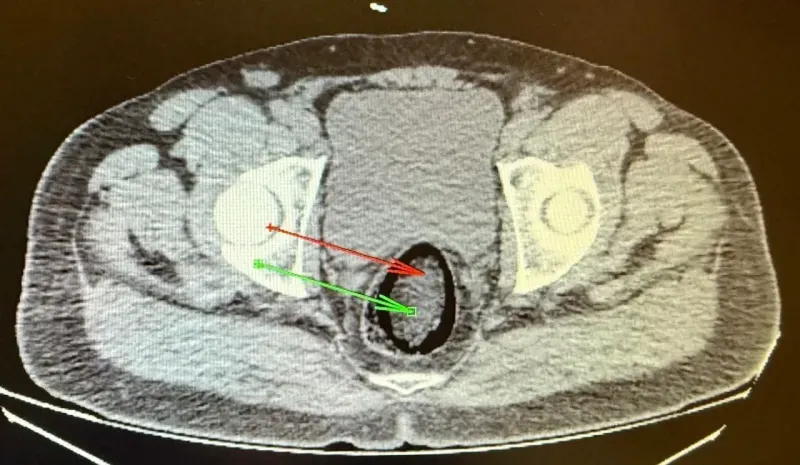

Kars Emniyet Müdürlüğü Narkotik Suçlarla Mücadele Şube Müdürlüğü ekipleri, Digor-Kars kara yolunda yaptığı uygulamada, yolcu otobüsünde arama yaptı. Polis, hareketlerinden şüphelendiği F.H.'yi gözaltına aldı. Kars Harakani Devlet Hastanesi'ne götürülen F.H.'nin çekilen röntgeninde, makatında uyuşturucu tespit edildi. 105,98 gram metamfetamin, cerrahi operasyonla çıkarıldı. Emniyetteki işlemlerinin ardından adliyeye sevk edilen şüpheli, çıkarıldığı hakimlik tarafından tutuklandı.